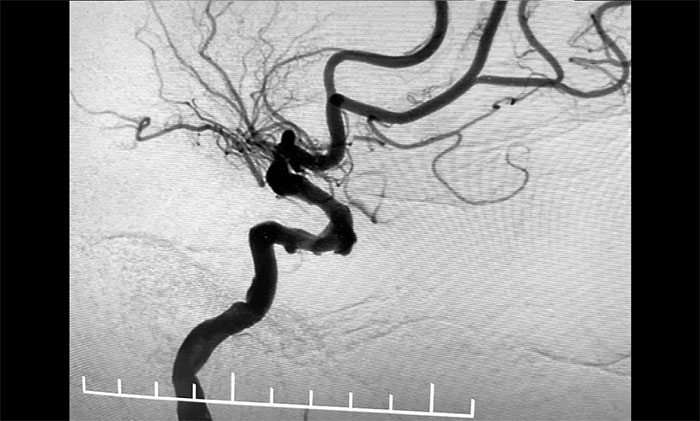

術中,席剛明教授、王貴平博士克服血管迂曲困難,經(jīng)過多次嘗試,多次球囊擴張、“按摩”后,最終順利釋放密網(wǎng)支架至左頸內動脈眼動脈段、左頸內動脈床突段、左頸內動脈海綿竇段。造影及3D造影見,動脈瘤瘤內造影劑明顯滯留,左頸內動脈、左大腦前動脈顯影可,載瘤動脈通暢,獲得了理想的血管重建。復查造影,左頸總動脈造影見左頸總動脈、左頸內動脈、左大腦前動脈顯影可。CT見支架打開貼壁滿意,XperCT未見顱內出血,手術圓滿完成,順利拆除“不定時炸彈”并打通大腦生命線。

▲ 頸動脈重度狹窄解除,打通大腦生命線

▲ 順利拆除“不定時炸彈”

術后,患者順利蘇醒,無新發(fā)神經(jīng)功能缺損,頭暈癥狀明顯改善。目前,患者已康復出院。